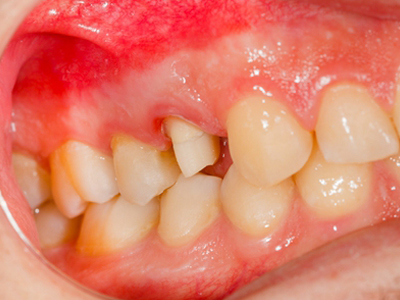

牙龈退缩牙龈萎缩露出牙根图

牙龈退缩发作于上排尖牙和磨牙处,导致牙根暴露在外,伴有牙齿松动、口臭、牙根面敏感等症状,是由于刷牙不当、牙周炎等因素引起。